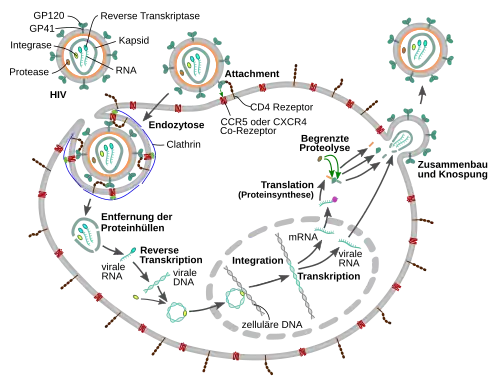

Zur Vermehrung benötigt das Virus Wirtszellen, die den CD4-Rezeptor auf der Oberfläche tragen.[79] Dies sind vor allem CD4-tragende T-Helferzellen (CD4+-Zellen). Als hauptsächliches Reservoir für die humanen Immundefizienz-Viren dienen die follikulären T-Helferzellen in den Lymphfollikeln des Körpers, die rund zwei Prozent der CD4+-Zellen ausmachen.[80][81] T-Helferzellen unterstützen andere Weiße Blutzellen bei immunbiologischen Prozessen, wie der Reifung der B-Lymphozyten zu Plasma- und Gedächtniszellen oder der Aktivierung zytotoxischer T-Lymphozyten und Makrophagen. Neben T-Lymphozyten besitzen auch Monozyten, Makrophagen und dendritische Zellen CD4-Rezeptoren. Latent infizierte ruhende CD4+-T-Zellen (T-Gedächtniszellen) stellen langlebige Reservoire für HIV dar und sind der Grund, dass HIV trotz wirksamer antiretroviraler Medikamente bisher nicht eradiziert werden kann und es nach Absetzen der Therapie immer wieder zu Rezidiven kommt.[82][83][84]

Fusion mit der Wirtszelle

1. Das Oberflächenprotein gp120 bindet an die CD4-Rezeptoren.

2. Konformationsänderung in gp120 ermöglicht eine nachfolgende Interaktion mit CCR5.

3. Die distalen Spitzen von gp41 dringen in die Zellmembran ein.

4. Durch die Bindung kommt es zu einer Konformationsänderung im Transmembranprotein gp41 („Schnappfedermechanismus“). Dieser Prozess verschmilzt die virale und zelluläre Membranen miteinander.

Um mit der Zellmembran der Wirtszelle verschmelzen zu können, binden die Oberflächenproteine gp120 an die CD4-Rezeptoren. Durch die Bindung kommt es zu einer Konformationsänderung im Transmembranprotein gp41, ein Mechanismus, der einer „Schnappfeder“ oder einer „Mausefalle“ ähnelt.

Neben den CD4-Rezeptoren sind weitere Co-Rezeptoren an der Bindung des HI-Virus an weiße Blutzellen beteiligt:[85] Die Chemokin-Rezeptoren CCR5 an monozytären Zellen und CXCR4 an T-Zellen sind an der Bindung beteiligt.[86][87] Die unterschiedliche Ausprägung dieser Rezeptoren beeinflusst die Ansteckungswahrscheinlichkeit und den Verlauf der HIV-Infektion.[88] Moleküle, die die CCR5-Rezeptoren blockieren, gehören zur Wirkstoffgruppe der Entry-Inhibitoren, spielen in aktuellen HIV-Therapien jedoch eine untergeordnete Rolle.[89][90]

Transport zum Zellkern und Zerfall des Virus-Kapsids

Einbau des HI-Virus-Genoms in die Wirtszelle

Das HIV baut zur Vermehrung seine Erbsubstanz, die bei ihm in Form eines RNA-Genoms vorliegt, nach der sogenannten reversen Transkription in die doppelsträngige DNA des Genoms der Wirtszelle ein.[97] Die Umwandlung von viraler RNA in provirale DNA im Cytoplasma der Wirtszelle durch das Enzym Reverse Transkriptase ist ein entscheidender Schritt im Reproduktionszyklus der Retroviren; beim HI-Virus ist dieser Prozess extrem fehlerbehaftet, was zu einer wiederholten Mutation des Virus' führt, welche wiederum einen Hauptgrund für die schwierige Bekämpfung darstellt. Da die Reverse Transkriptase von Retro- und Hepadnaviren sich stark von anderen reversen Transkriptasen wie der humanen Telomerase unterscheidet, stellt sie ein wichtiges Ziel therapeutischer Intervention dar und ist Ansatzpunkt zweier pharmakologischer Wirkstoffklassen.

Nach reverser Transkription und Transport in den Zellkern schließt sich die Integration des Virus-Genoms in das menschliche Erbgut durch ein weiteres virales Enzym an, die Integrase.[98][99] Die virale DNA wird schon vor der Integration abgelesen, dabei werden auch bereits die viralen Proteine gebildet. Demnach liegt die HIV-DNA als integrierte und nicht-integrierte Form vor. Auch existieren zirkuläre Formen von HIV-DNA.

Das nun als integriertes Provirus vorliegende virale Genom zeigt einen charakteristischen Aufbau, wobei die codierenden Bereiche auf beiden Seiten von identischen regulatorischen Sequenzen, die im Verlauf der reversen Transkription generiert wurden, den sogenannten LTRs, flankiert sind. Der Promotor, unter dessen Kontrolle die Transkription der verschiedenen mRNAs erfolgt, liegt im Bereich des LTR und wird durch das virale Protein TAT aktiviert. Eine ungespleißte RNA dient als virales Genom für die nächste Generation von HI-Viren und als mRNA für die Translation eines Gag (Gruppenspezifisches Antigen) sowie mittels einer in einem von 20 Fällen vorkommenden Verschiebung des Leserasters eines Gag-Pro-Pol-Vorläuferproteins. Gespleißte RNAs codieren für das Hüllprotein Env sowie die ebenfalls im 3'-Bereich befindlichen weiteren Proteine. HIV codiert für 16 Proteine.[100]

Im weiteren Verlauf folgt die Morphogenese, das heißt, über verschiedene Interaktionen finden die viralen Bestandteile wie Gag-, Pro-pol- und Env-Vorläuferproteine sowie die RNA zusammen und formen sich zu zunächst unreifen Virionen, die sich von der Plasmamembran abschnüren. Durch weitere Reifungsprozesse entsteht das reife Viruspartikel, bereit für die Infektion der nächsten Zelle. Zu den Reifungsprozessen gehört insbesondere die Spaltung der Vorläuferproteine – teils durch die virale Protease, teils durch zelluläre Enzyme – in ihre einzelnen Bestandteile, also von Gag in Matrix-, Kapsid- und Nukleokapsidprotein, Pol in Protease, Reverse Transkriptase mit RNase H und Integrase sowie Env in Oberflächen- und Transmembraneinheit. Die neugebildeten Tochtervirionen verlassen die Zelle durch Knospung. Beim Zusammenbau wird das HIV mit dem zellulären Protein Cyclophilin A bedeckt.[101] Dabei bindet je ein Cyclophilin A an zwei Hexamere des Kapsidproteins, wodurch es das Kapsid stabilisiert und maskiert vor intrazellulären Mechanismen der angeborenen Immunantwort in Makrophagen und dendritischen Zellen.[101]